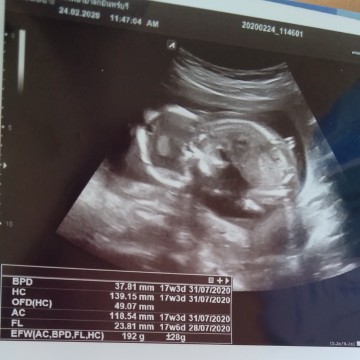

ตอนน้องได้4เดือนตอนนี้น้องได้8เดือนแล้วค่ะ